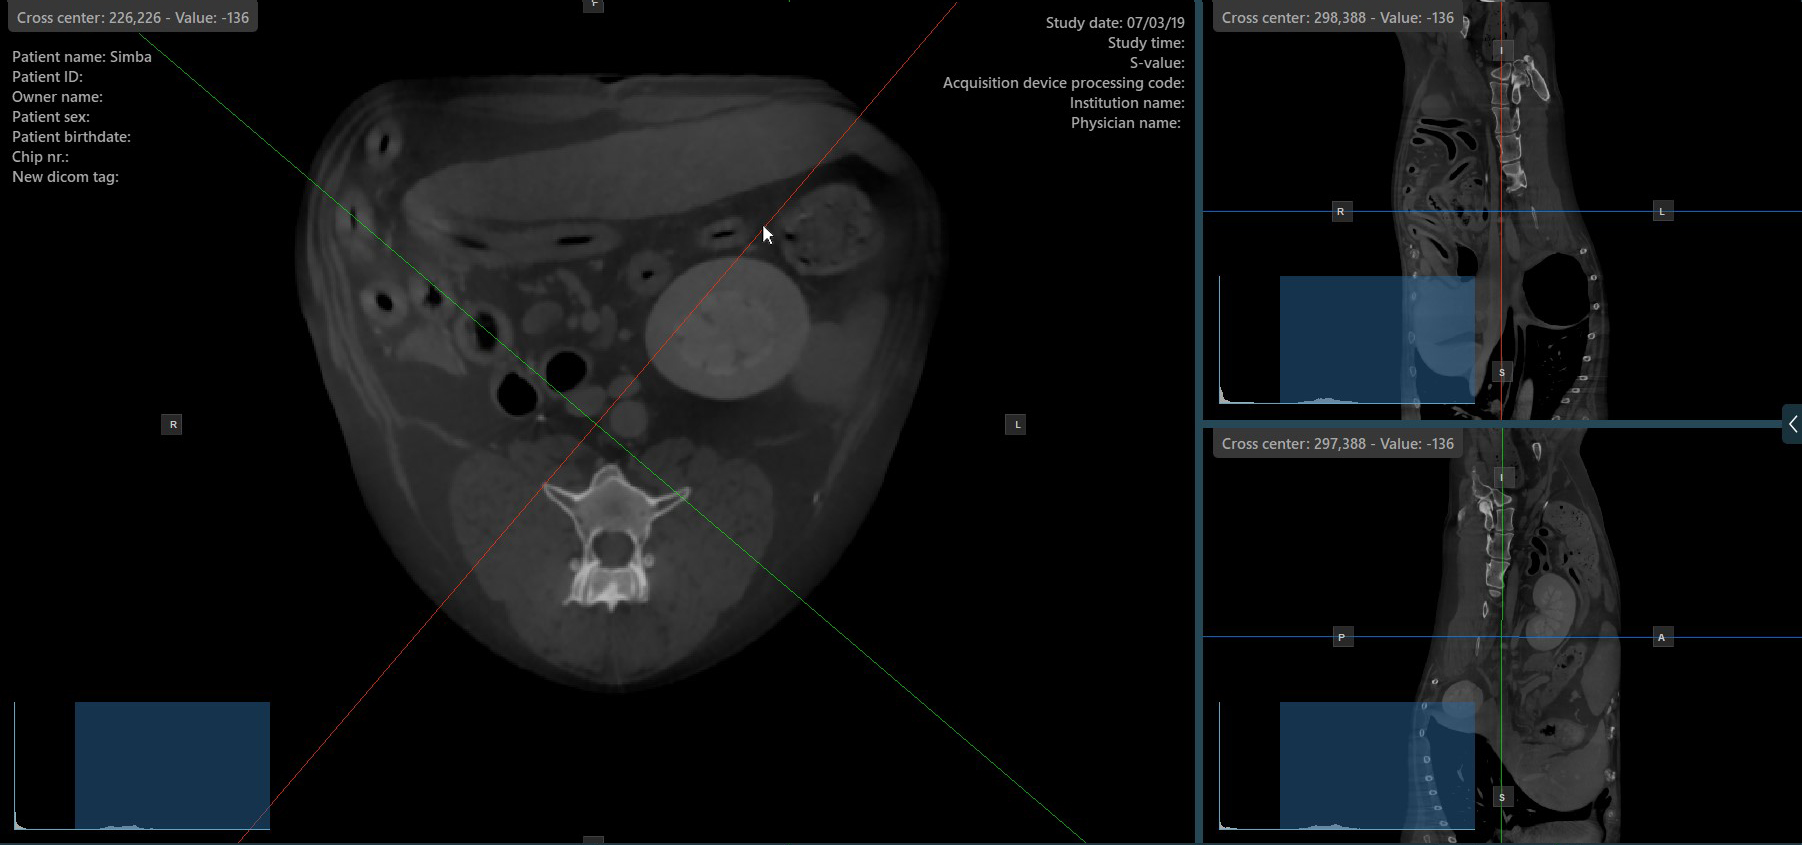

Press the Perpendicular Slicers

icon in the left toolbar to activate simultaneous rotation of the slicers. Regardless of their previous orientation, the slicers are repositioned to be perpendicular to each other.

Toggle the Perpendicular Slicers

option to switch the active mode of the slicers at any time, or choose one of the Tools -> Perpendicular Slicers

or Tools -> Separate Slicers

options from the CT Viewer menu.